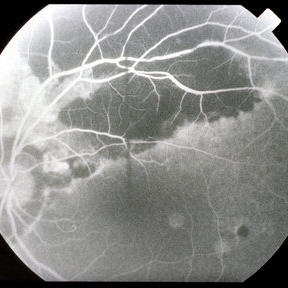

Large Sub-RPE and Subretinal Hemorrhage Nasal to the Disc 3

Mar 14 2013 by Maurice F. Rabb

The left eye of 59 year-old black women remained stable with 20/25 vision until she presented a 9-day history of a shadow in the left eye. She had a large sub- RPE and subretinal hemorrhage nasal to the disc. Fluorescein angiography did not identify a site of chooroidal neovascularization. No treatment was done.

Condition/keywords: 20/25, left eye, retinal pigment epithelium, shadow, subretinal hemorrhage